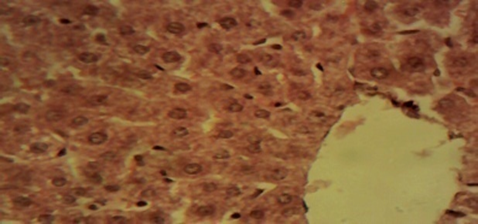

Compared to rats in the control and in the therapeutic dose groups, that showed normal hepatic lobules composed of normal hepatocytes arranged in interconnecting cords around the central vein in their histo-architecture (Figure 1 & Figure 2), mild to moderate changes including hepatocellular necrosis observed in the liver sections of the other groups (Figure 3–5) were moderate to severe in the group of rats exposed to overdose of AL together with MSG (Figure 6).

Figure 1 Photomicrograph of the liver sections from rats in the control showing normal hepatic lobules composed of normal hepatocytes arranged in interconnecting cords around the central vein (×400).

Figure 2 Photomicrograph of the liver of the therapeutic dose animal showing normal hepatic histomorphology for laboratory rodents (×400).